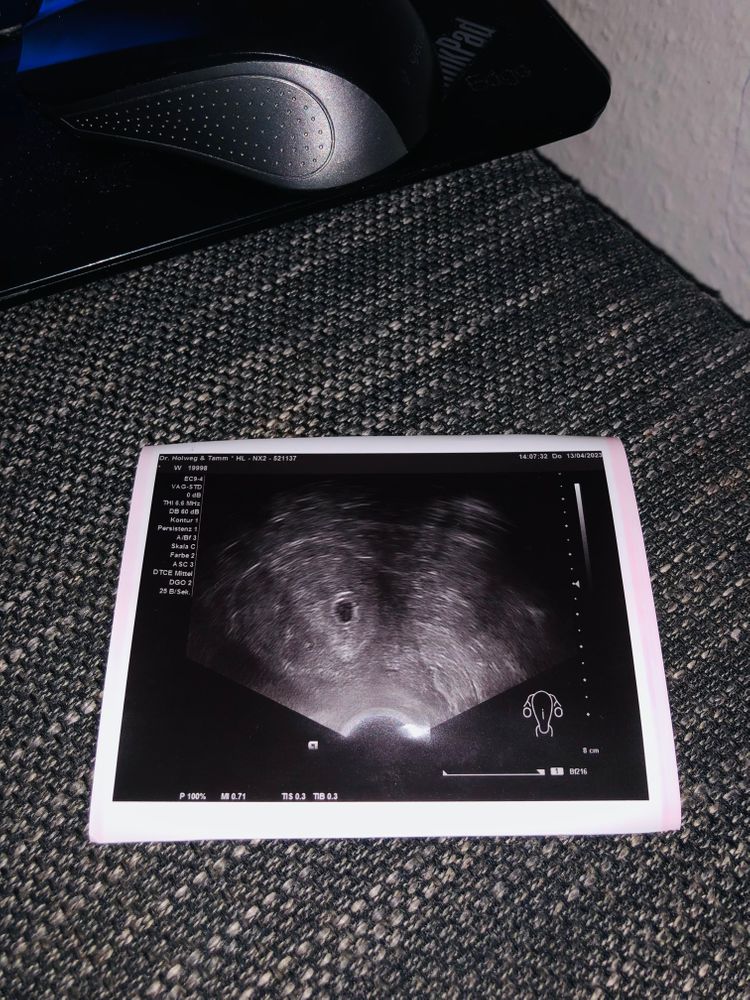

Узи 5 недель.

Два жт, значит вышло две яйцеклетки, одна просто чуть позже оплодотворилась и пя совсем крошечное и не видно ещё. А может две вышло яйцеклетки, но одна не оплодотворилась (жт всё равно будет).